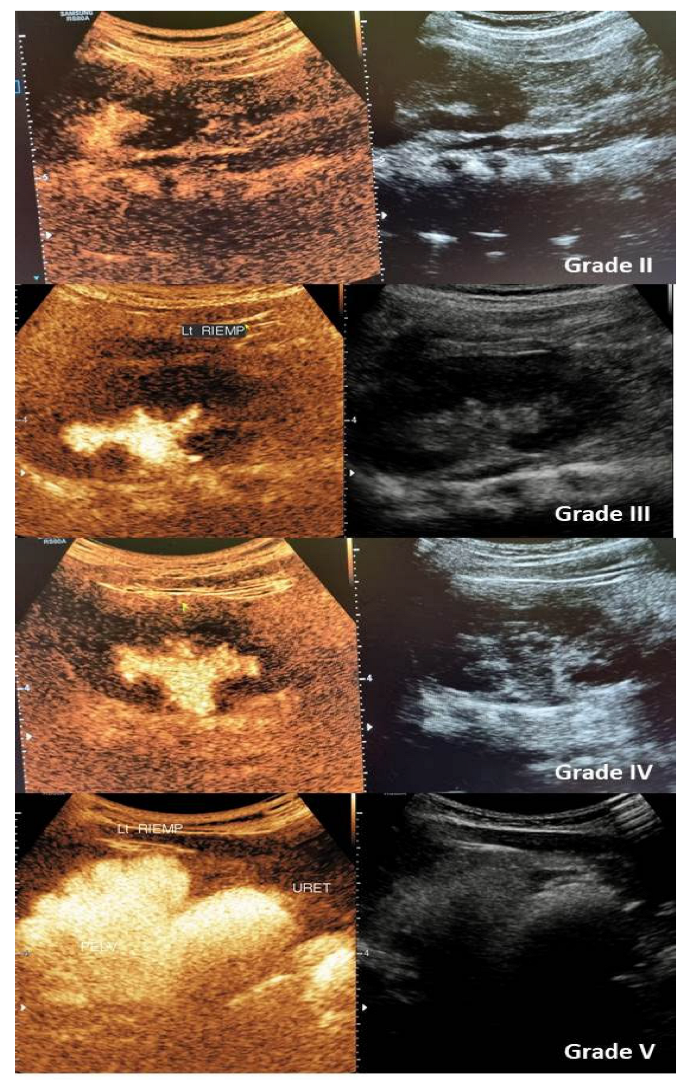

- Yi, H.; Cui, X.; Cai, B.; Qiu, L.; Song, P.; Zhang, W. A quantitative grading system of vesicoureteral reflux by contrastenhanced voiding urosonography. Med. Ultrason. 2020, 22, 287–292. [Google Scholar] [CrossRef]